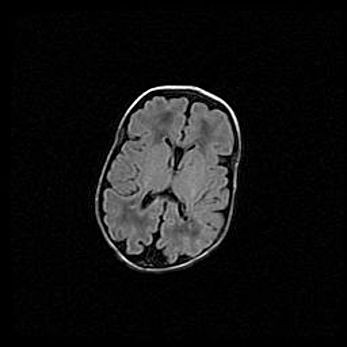

Открытая гидроцефалия.

Возраст: 9 месяцев 12 дней

Вес: 6800 г

Пол: мужской

Окружность головы: 41,5 см

Срок гестации: 28 недель

Гидроцефалия головного мозга у новорожденных имеет характерный признак: опережающий рост окружности головы приводит к визуально хорошо определяемой гидроцефальной форме сильно увеличенного в объёме черепа. Детские неврологи определяют следующие симптомы гидроцефалии у грудничков: выбухающий напряжённый родничок, частое запрокидывание головы, смещение глазных яблок к низу.